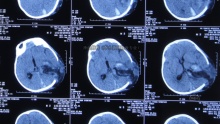

脑室双侧侧脑室加四脑室引流

神经内科-神经内科

雷敬 关注

桃源县人民医院前天12:47 56阅读 0评论 0点赞 -